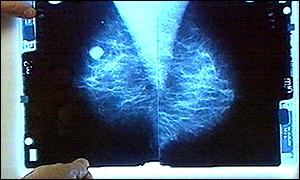

| Tuesday, 5 November, 2002, 10:25 GMT UK cuts cancer deaths  Cancer deaths have fallen in the UK Britain has succeeded in significantly cutting cancer death rates, moving from having the third highest to the fifth lowest in Europe. Professor Peter Boyle, of the European Institute of Oncology, presented the data to the Britain Against Cancer conference in London on Tuesday. He told the conference that the UK, along with Luxembourg, has achieved a goal of cutting cancer deaths in men by 15%.